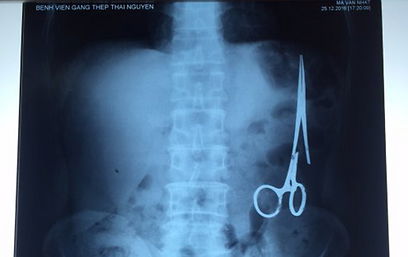

הוא התלונן על מיחושים קלים בבטן ונשלח לבדיקת אולטרסאונד שהצביעה על ממצא חשוד בבטנו. האיש נשלח לצילום רנטגן שהראה לתדהמת הרופאים כי מלקחיים רפואיים נותרו בבטנו, סמוך למעי הגס.

החולה הועבר מיד לחדר הניתוח, שם שלפו הרופאים מבטנו את המלקחיים שכבר העלו חלודה. הרופאים מסרו לאחר מכן כי המלקחיים דחקו חלק מאיבריו הפנימיים של החולה ויכלו לסכן אותו.